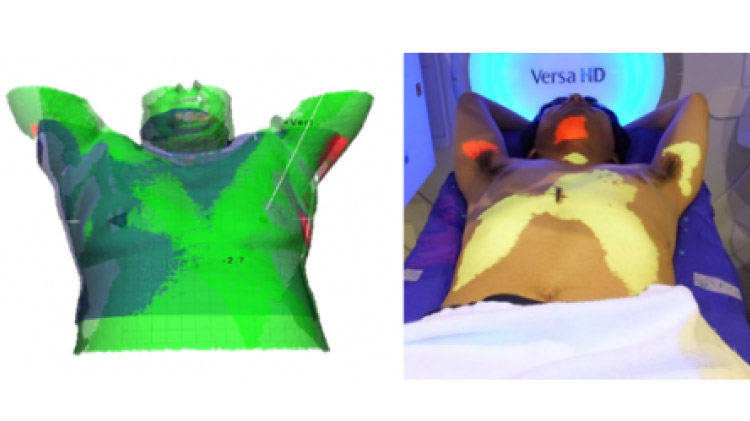

Surface IGRTシステム(体表⾯光学トラッキングシステム)︓Catalyst(C-RAD社製)

患者体表画像を⽤いて画像誘導放射線治療を⾏います。可視光を⽤いて体表⾯画像を画像化しますので不必要な被曝がなく、簡便に何度でも⾏うことができます。取得された画像を基準画像と⽐較し、位置補正を⾏います。主に標的が体表⾯に近い乳房照射など、また呼吸同期・停⽌システム、照射中のモニタリングの⼀環として⽤いられます。